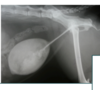

what is this?

Small kidney and abnormal ca

Was ist Das?

IVU

Mis-shapen – fibrotic

Small